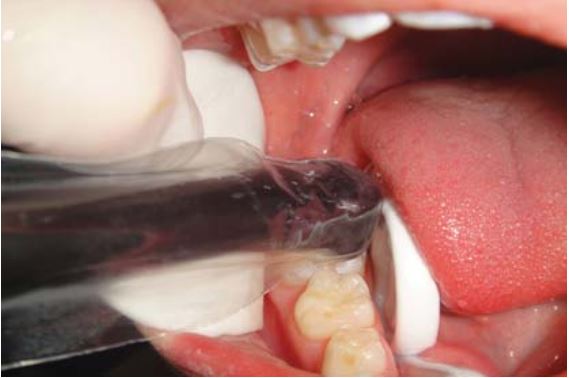

Chiếu đèn

Chiếu đèn không đúng có thể làm ảnh hưởng đến sự lưu giữ của miếng trám. “Sealant trong” thì trùng hợp tốt hơn “sealant đục” (Yu, 2009). Đèn trám nên chạm vào đỉnh múi để đảm bảo sealant trùng hợp hoàn toàn (H9.7).

Mỗi loại vật liệu đều có những thông tin về bước sóng riêng biệt để kích hoạt.